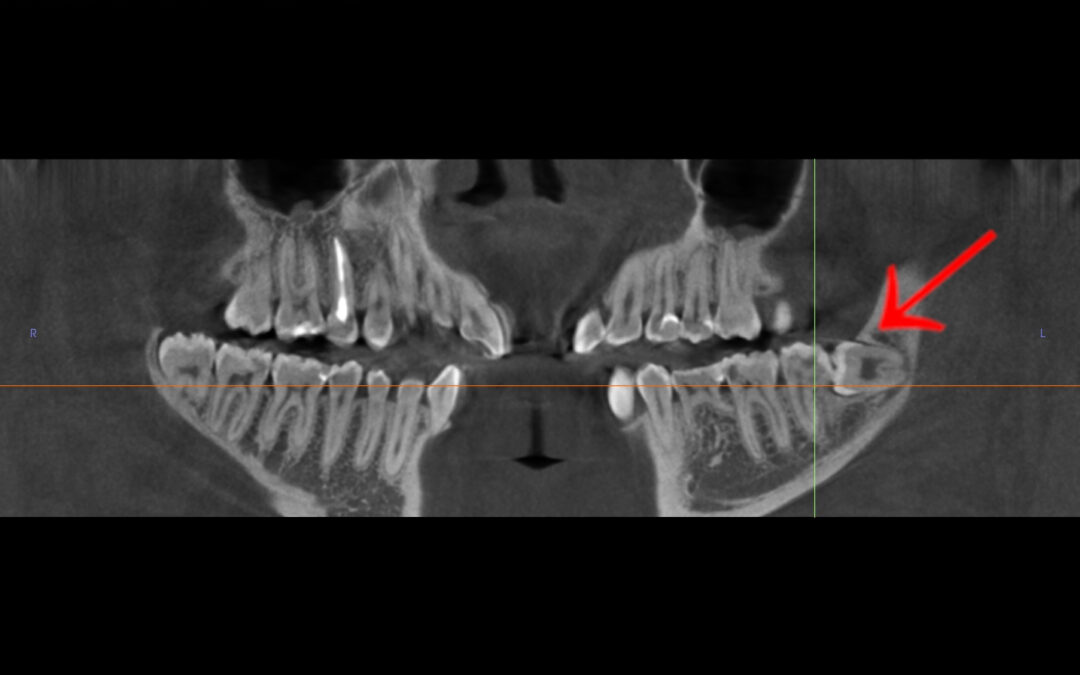

🦷 CASE STUDY: Usunięcie zatrzymanej ósemki w orientacji poziomej — historia pani Igi (20 lat) Pani Iga zgłosiła się do naszego Instytutu z powodu zatrzymanej dolnej ósemki po lewej stronie, która — jak pokazało badanie tomograficzne — była ustawiona poziomo, głęboko w...